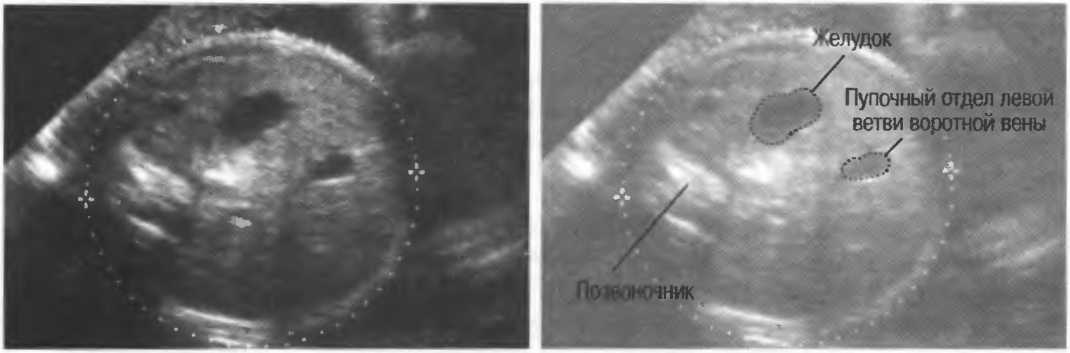

- При удовлетворительном качестве изображения можно получить изображение полости прозрачной перегородки головного мозга у 35-недельного плода (рис. 23). Этот тест можно использовать для контроля качества в случаях, когда нет фантома. Данный тест необходимо проводить каждые 3 мес.

Рис.23а. На любом приборе должна визуализироваться полость прозрачной перегородки головного мозга 35-недельного плода.

Рис.23б. На аппарате высокого класса полость может визуализироваться в более ранние сроки беременности.

2. Верхняя брыжеечная артерия должна визуализироваться в виде округлого или овального эхонегативного образования, расположенного рядом с поджелудочной железой у здорового взрослого обследуемого (рис. 24). Наиболее простым способом проверки качества изображения является визуализация своей собственной верхней брыжеечной артерии. Сохраняйте эхограммы после каждого исследования для сравнения.

Рис.24. Поперечный срез: верхняя брыжеечная артерия представлена эхонегативным округлым образованием, окруженным эхогенной жировой клетчаткой, расположенным близко к поджелудочной железе.

- Печеночные вены диаметром всего 3 мм должны визуализироваться при сканировании под углом 45° к поверхности нормальной печени (рис. 25).

Рис.25. Аппарат хорошего качества должен позволять визуализировать печеночные вены диаметром 3 мм. Этот тест может регулярно использоваться для контроля качества изображения.

4. У здоровых обследуемых паренхима печени должна быть немного более эхогенна. чем кора рядом расположенной почки (рис. 26).

Рис.26. Продольный срез через печень и правую почку: нормальная паренхима печени более эхогенна, чем паренхима нормальной почки. Это еще один способ проверки качества изображения.